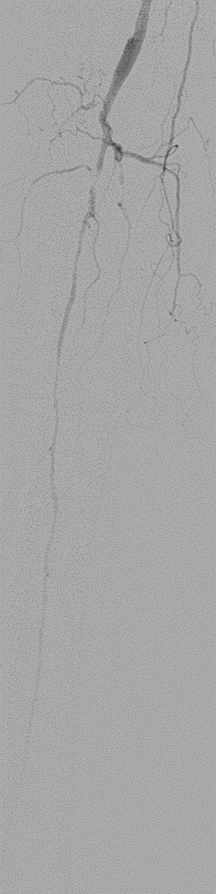

★ Case 1

noproximal stump in SFA,>250mm

★ Case 2

significantdistal collaterals